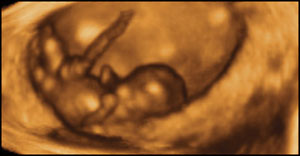

10 týdnů, 6 mm

V deseti týdech plod může plod různě pohybovat rukama a nohama.